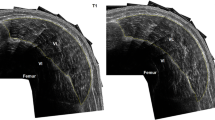

Muscle CSA

The CSA of the right thigh muscles was measured using a peripheral quantitative computed tomography (pQCT; XCT 3000, Stratec Medizintechnik GmbH, Pforzheim, Germany) scanner. Cramer et al. (2007) showed that when compared with the magnetic resonance imaging (MRI) scanner (the current gold-standard), the pQCT provided a reliable and valid measurement of muscle CSA with a correlation between measurements of r = 0.991. The subject sat upright with their leg fully extended (180°), and the scan was taken at the midpoint of the thigh (i.e., at 50% of the distance between the greater trochanter and lateral epicondyle of the femur). All of the scans were performed by the same investigator. Muscle CSA was calculated using the software provided by the manufacturer. This procedure has been described in more detail in a previous publication (DeFreitas et al. 2010).